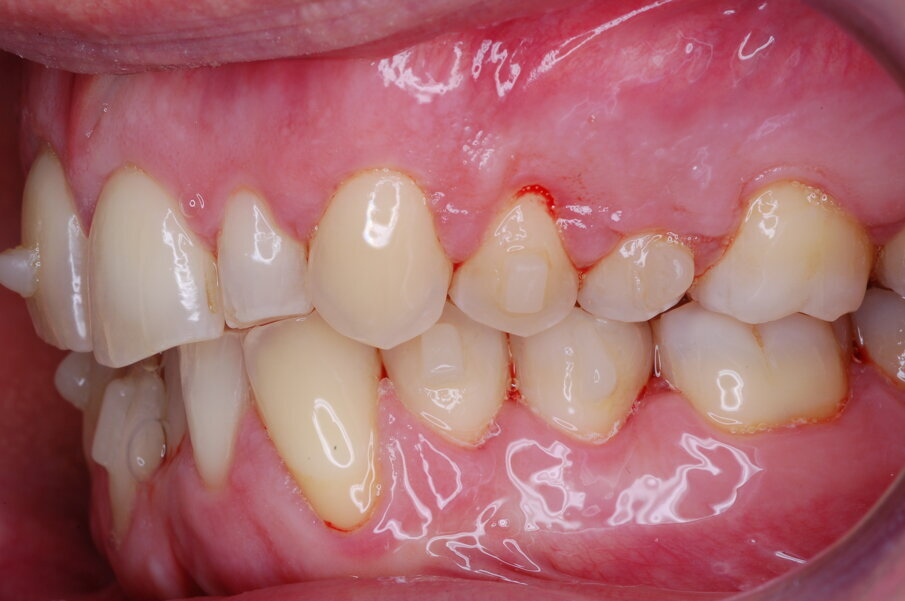

Diagnosi ed eziologia Un uomo sano di 39 anni si è presentato nel nostro studio ortodontico lamentando un aspetto dentale poco attraente e la paura della chirurgia ortognatica proposta da un altro ortodontista. Clinicamente, il profilo del paziente era rettilineo e la vista frontale non mostrava alcuna asimmetria facciale. L’esame funzionale non ha rivelato alcuna deviazione mandibolare o riduzione dei movimenti. Il paziente non aveva dolori articolari e non sono stati rilevati rumori articolari. Era presente una lieve occlusione molare bilaterale di Classe II, un morso aperto e un grave affollamento in entrambe le arcate. L’affollamento era particolarmente grave nell’arcata mandibolare, sebbene mancasse l’incisivo centrale mandibolare destro. Gli incisivi mascellari erano di piccole dimensioni, suggerendo una discrepanza dell’indice di Bolton se fossero stati presenti tutti e quattro gli incisivi mandibolari. Erano inoltre presenti un morso incrociato nella regione dell’incisivo laterale superiore sinistro e una grave rotazione distale del secondo premolare mandibolare sinistro (Figg. 1-8).

Figg. 1-8_Fotografie facciali e intraorali pre-trattamento.